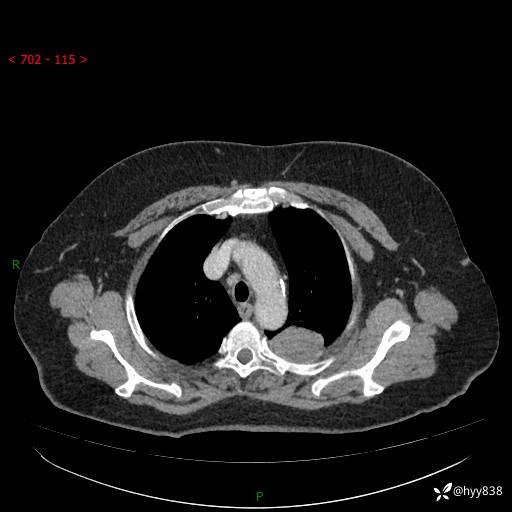

老年女性,左上肺结节8年。典型又不典型,看你如何解读---结果公布(值得分析)

主诉:检查发现左上肺结节8年,较前增大。

简要病史:患者于8年前体检行胸部CT检查发现左上肺结节(4mm),患者平素间断咳嗽咳痰,无心慌、胸闷、胸痛、呼吸困难、低热、盗汗,无头痛、头晕,无腹痛、腹胀等不适,未行特殊处理,定期复查。2023-09-21胸部CT示左上肺结节(2cm)较前增大,2024-02-01胸部CT示左上肺尖后段(39*32mm),左侧肺门及纵隔淋巴结增大,现患者欲求手术治疗,遂来我院就诊,以“左上肺结节”收入我科。 患者自起病以来,精神可,睡眠可,饮食可,大小便正常,体重无明显改变。

辅助检查:CT

胸部CT平扫

增强(动脉期+静脉期)